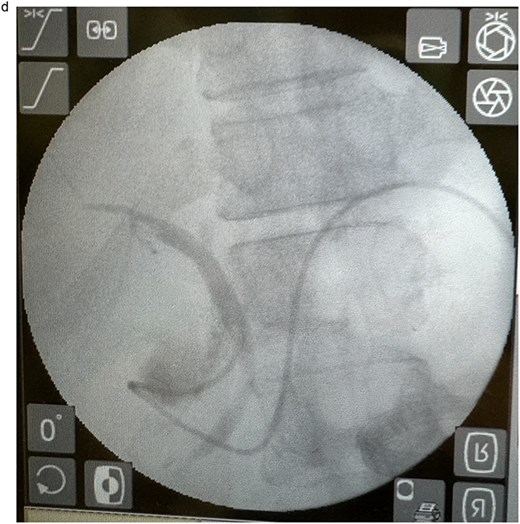

In view of the ongoing leakage and the hostile operative field, a third intervention was undertaken on postoperative day 24 following the second surgery. After multidisciplinary discussion, a combined surgical–endoscopic approach was undertaken in collaboration with internal medicine specialists. Intraoperative findings revealed dense adhesions from prior surgeries and a 0.5-cm perforation at the proximal duodenal stump, located near the ampulla of Vater. Initial endoscopic retrograde cholangiopancreatography (ERCP) was unsuccessful due to limited ampullary access; thus, EUS-CDS with ENBD placement was performed as an alternative strategy. From the duodenal bulb, the common bile duct (CBD) measured 4.7 mm on EUS, and Doppler confirmed no intervening vessels (Figs 4a and 4b). A 19-gauge EZ Shot 3 needle (Olympus) was used to puncture the extrahepatic bile duct, and bile aspiration followed by contrast injection confirmed correct positioning (Fig. 4c). A VisiGlide 2 angled guidewire (0.025 inch) was advanced into the right intrahepatic duct, and the tract was dilated using an ES dilator. A 7-Fr ENBD catheter was subsequently deployed across the choledochoduodenostomy under fluoroscopic guidance, achieving effective biliary drainage (Figs 4d and 4e). In addition, a 16-Fr Foley catheter was inserted into the duodenal perforation as a duodenostomy tube (Fig. 4f) for external drainage, and six closed wound vacuum drains were placed for peritoneal irrigation and drainage.